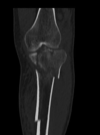

Fratura do platô tibial lateral - Schatzker tipo 2 (traço de fratura + depressão do plato lateral).